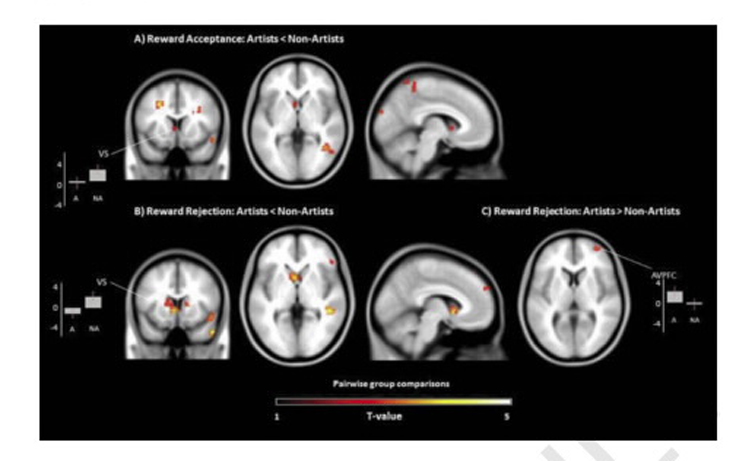

Когда творческие люди находили «денежный» цвет, их мозг показывал очень слабую активность в области полосатого тела — участке, который отвечает за реакцию на вознаграждение. Зато когда художники находили цвета, но не получали за это деньги, повышенная активность наблюдалась в передней префронтальной коре, которая отвечает за выработку дофамина, влияющего на чувство удовлетворения.

Исследователи заключили, что мозг творческих людей проявляет интерес только к самому процессу, не беря в расчет материальное вознаграждение. Кроме того, «художники» могут работать гораздо лучше, когда знают, что не получат за это деньги.